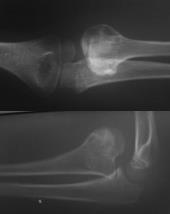

Considere a imagem a seguir:

As radiografias revelam Osteocondroma da porção: